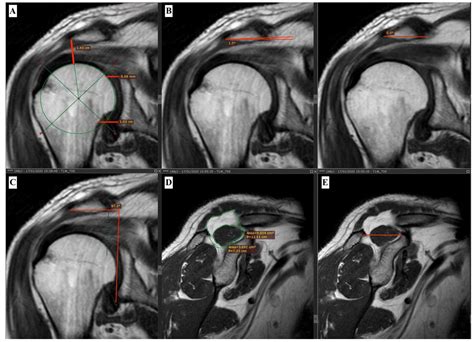

• Musculoskeletal Imaging: Orthopedic surgeons and rheumatologists use MRI without contrast to evaluate joint injuries, ligament tears, and bone abnormalities. The high-resolution images provide valuable insights into the condition of muscles, tendons, and ligaments.